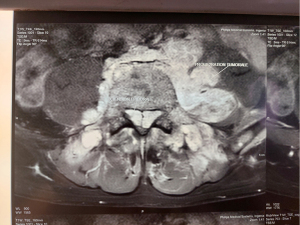

Tumor markers assayed postoperatively: alphafoetoprotein 8,937.39 ng/mL lacticodehydrogenase 1,369 IU/L, chorionic gonadotropic hormone beta less than 1.20 mIU/mL. One month after the operation, the patient developed a ponytail syndrome associated with stepping. An additional medullary MRI revealed a tumor proliferation next to the fifth lumbar vertebra with epidural extension responsible for spinal cord compression, in addition to bone metastases involving the axial skeleton, the iliac wings with epiduritis opposite the fifth dorsal vertebra (Figures 1,2).